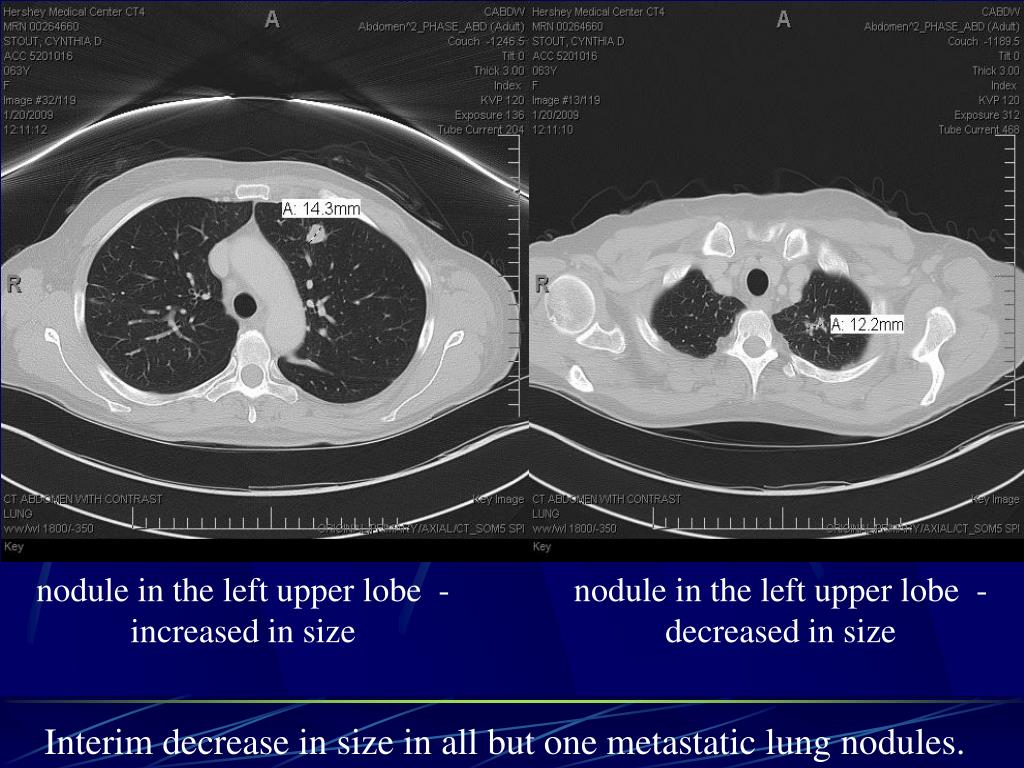

4. nodule in the left upper lobe - increased in size nodule in the left upper lobe - decreased in size Interim decrease in size in all but one metastatic lung nodules.